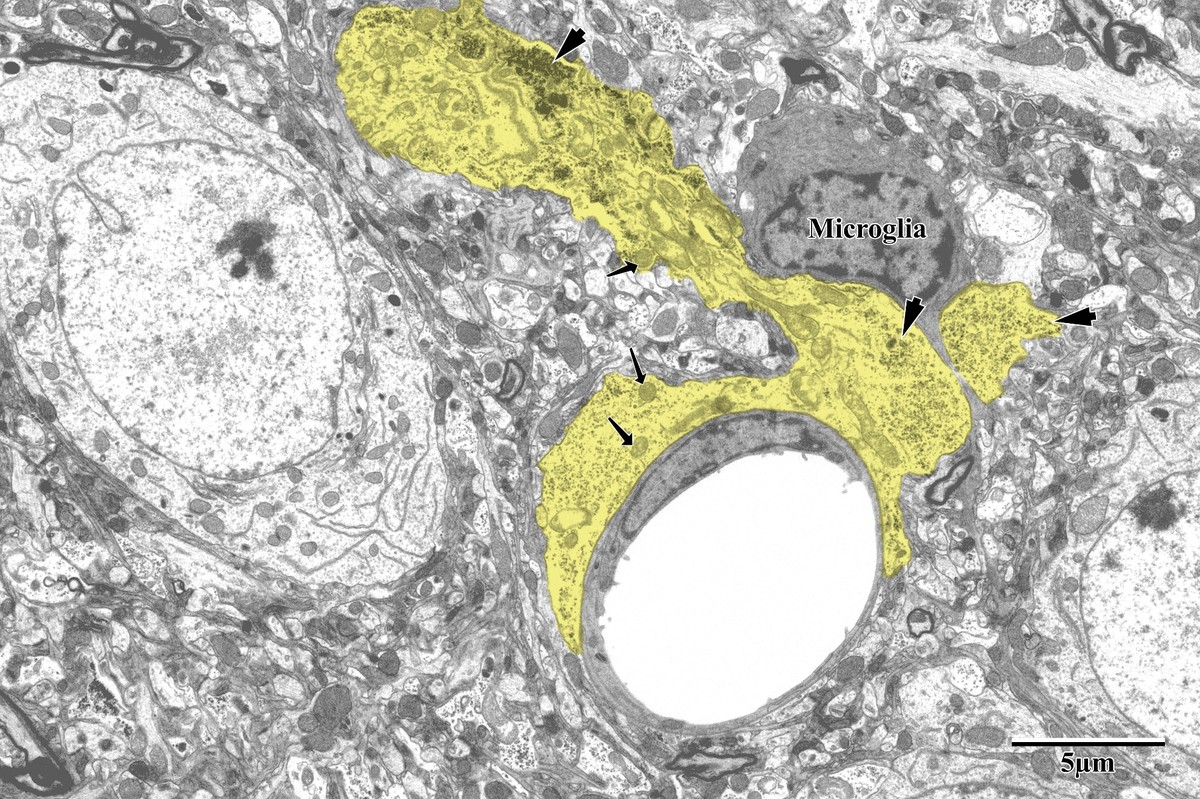

Astrocytic Inflammation & Mitochondrial Changes

Astrocytes responded dramatically to ischemic injury, showing increased process area and reactive morphology in the peri-infarct zone. Astrocytic processes were traced and pseudocolored yellow for quantification, revealing glycogen granule accumulation, swollen mitochondria, and extensive perivascular endfeet coverage around capillaries.

Reactive Astrocytosis

Pseudocolored astrocytes (yellow) surrounding neurons (blue) in peri-infarct zone

Peri-infarct zone: reactive astrocytes (yellow) surrounding pyramidal neurons (blue). Note the dramatically increased astrocytic coverage compared to control tissue, with microglia also visible. From Bayati, BSc Honours Thesis 2018.

Astrocytic endfeet around capillary with microglia

Astrocytic endfeet (yellow) surrounding a capillary in the peri-infarct zone. Lighter mitochondria (arrows) and glycogen granules (arrowheads) are identifying features. Microglia visible in close proximity, suggesting active inflammation. From Bayati, BSc Honours Thesis 2018.